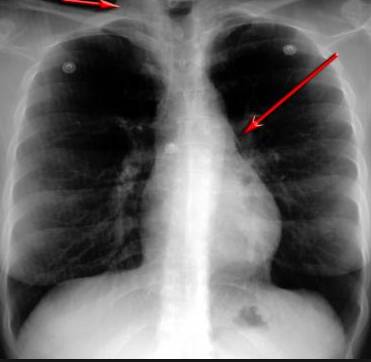

并且,因為呼吸系統結構復雜,在體檢時醫生很難通過一種檢測手段,判定早期患者的病情。

把整個肺部看得清清楚楚!

使用這臺掃描儀,將直接把器官變成3D圖形!細微的毛細血管,幾毫米大的肺泡和支氣管,都將能看的一清二楚!

你的每一個氣泡,每一段支氣管,哪兒有病變都清清楚楚的將展示在醫生面前!

也就是說在一切都還沒開始惡化前,把這些有問題的器官組織都暴露的一清二楚:

不同于CT掃描,需要從同一角度,拍下無數張器官二維圖,從而搭建3D器官結構圖那般費時費力。

沒有這項新技術,醫生在做體檢的時候,很難通過一種測試斷定一個人是否有呼吸系統疾病。

可是現在他們不但能看到整個肺部的3維結構圖。還能看到空氣進入人體后的所有微小變動!